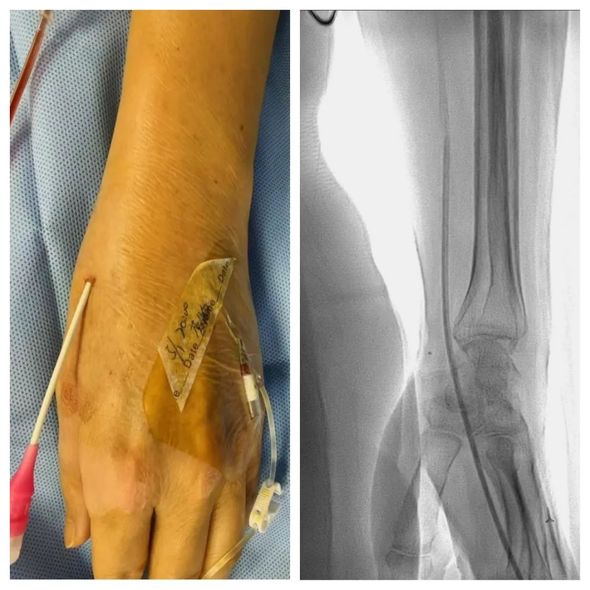

痔疮是最常见的肛肠疾病,任何年龄都可发病,素有“十男九痔、十女十痔”的说法。痔疮主要的临床表现是便血、异物脱出、或伴有疼痛、瘙痒等症状。痔疮发病部位在肛门,由于部位隐私,羞于就医,多存在长期地慢性失血,最终导致贫血。患者代女士,反复大便出血多年,碍于病变部位隐秘,不愿行外科手术治疗,多发打听得知可行介入微创治疗。此次因进食辛辣刺激食物后便血加重到我院就诊。介入科负责人莫庆国基于痔疮血供特点,结合患者实际病情与需求,制定在局部麻醉下经远桡动脉行痔疮动脉造影+栓塞术的治疗方案。征得患者同意后手术如期进行。

手术选取远桡动脉入路

术中部分图像

次日,患者激动的对莫庆国说,“真是太厉害了,今早排便一点血都没有了,手上也没有明显的手术切口,整个治疗过程简直太舒服了。”